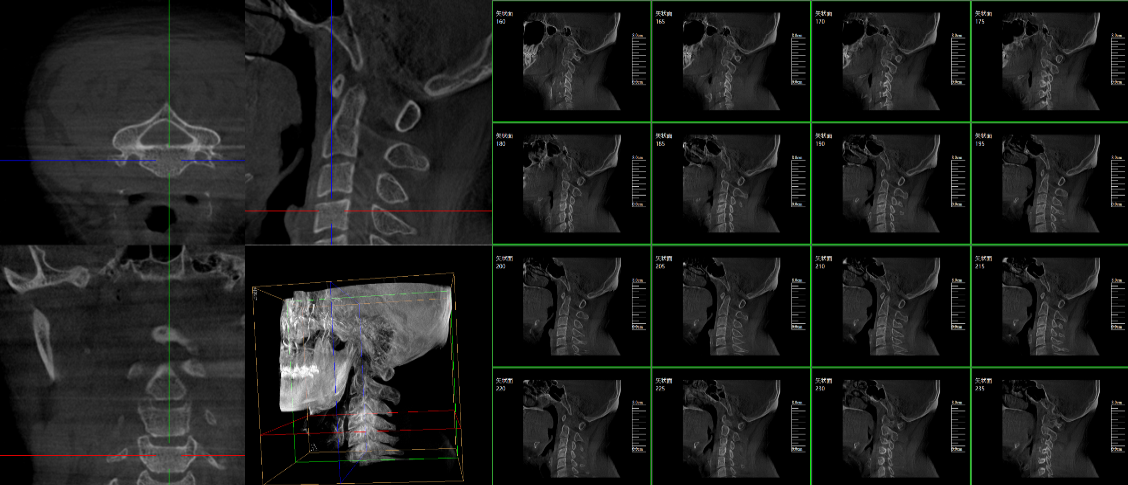

現在很多廠家或者經銷商都在推廣三維c型臂,那么,三維c型臂是什么意思?三維c型臂是一款新型C形臂,實現了術中影像從二維到三維的飛躍。通過不同方位的斷層圖像,能夠更清晰、完整地顯示椎體及其附件的解剖學結果,直觀地分析病變與周圍組織的立體空間關系,三維斷層成像能夠使手術模擬和手術方案的制定更加準確。

脊柱外科的應用:有研究表明,在三維c型臂圖像引導的下頸椎或胸椎后路螺釘置入術中,螺釘正確置入率可達92.7%,在三維c型臂圖像引導的椎間孔腰椎椎間盤融合術中,術者被輻射總量明顯降低。此外三維c型臂可以搭配骨科手術導航和機器人使用,能將該過程智能化和準確化,進一步提高螺釘的植入率。

截骨矯形外科中的應用:胸腰段是脊柱應力相對集中區域,因此,該節段更易發生骨折,且骨折術后更易并發角狀后凸畸形,大多數患者都需二次手術矯正。他們認為術中三維c型臂輔助后路螺釘置入并半椎體切除矯形治療兒童先天性脊柱后突畸形患者時,螺釘置入精度高且安全,截骨矯正效果滿意。

創傷外科的應用:由于創傷外科的患者多數為急、重癥患者,以致術前準備時間較短,很多都需行急診手術,三維c型臂可以在術中實時重建三維圖像,使手術醫生對一些復雜骨折更加充分的了解,并且能夠在術中即時校正螺釘的位置,更加精確地置入固定器材,減少術中及術后發生并發癥的幾率,極大限度地縮短螺釘置入時間。